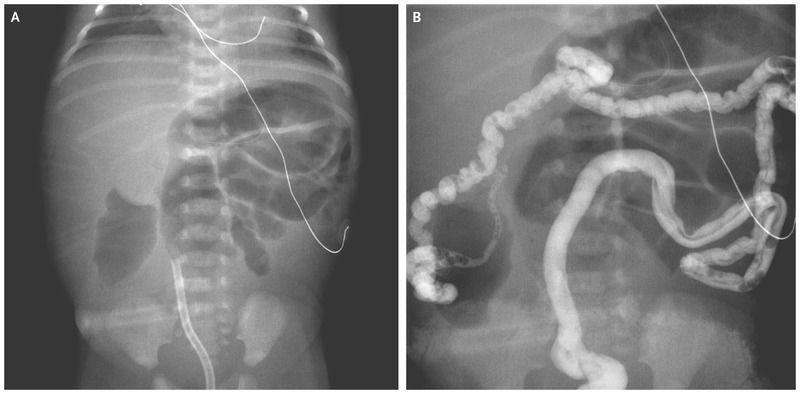

In a full-term newborn girl, abdominal distention with emesis and failure to pass meconium developed at 12 hours of age. A diagnosis of cystic fibrosis had been made during pregnancy, when genetic analysis of amniocentesis fluid showed the fetus to be heterozygous for known disease-causing mutations p.F509del and p.V603SfsX8 in the cystic fibrosis transmembrane conductance regulator (CFTR) gene. A radiograph of the abdomen showed dilated loops of small intestine that aroused concern for intestinal obstruction (Panel A). A water-soluble contrast enema showed microcolon and multiple filling defects throughout the colon and distal ileum (Panel B), findings that were consistent with a diagnosis of meconium ileus. Exploratory laparotomy with ileostomy was performed. Meconium ileus, which can be an early manifestation of cystic fibrosis, can also occur in extremely premature infants who have a very low birth weight. Obstruction in the ileum results from intraluminal accumulation of inspissated meconium. The differential diagnosis of delayed passage of meconium also includes Hirschsprung’s disease and the meconium plug syndrome. At 7 weeks of age, removal (takedown) of the patient’s ileostomy was performed. At 14 weeks of age, she underwent additional abdominal surgery because of the formation of a fistula that had connected the underlying bowel to the incision site of the former ileostomy.